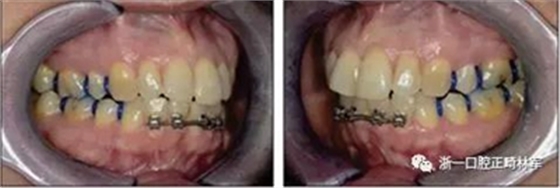

由于下頜中切牙間沒有間隙行下頜正中切開術(shù),故進行術(shù)前正畸擴展間隙。下頜前牙粘托槽,中切牙托槽成交放置,將中切牙牙根分開。使用0.018X0.018鎳鈦絲及置于下頜左、右中切牙之間的推簧推間隙。3個月后拍攝CBCT示已有足夠間隙行下頜正中截骨術(shù)。

手術(shù)前三周,上、下頜磨牙和前磨牙使用分壓圈進行分牙。術(shù)前一天,去除下頜切牙托槽,安裝hyrax擴弓器。

術(shù)后第9天開始旋轉(zhuǎn)擴弓器,每天轉(zhuǎn)2次,每次轉(zhuǎn)90度,即擴開0.5mm。每隔1周進行檢查,目標上頜擴開9mm,下頜擴開6mm。18天后,上頜中切牙間出現(xiàn)8mm間隙。下頜出現(xiàn)6mm間隙,(于13天出現(xiàn)后,停止旋轉(zhuǎn)擴弓器)。在擴弓器旋轉(zhuǎn)3天后,拍片發(fā)現(xiàn)左下頜中切牙遠中牙根中段有一條低密度陰影,臨床冷熱診反應(yīng)遲鈍,可能為術(shù)中損傷所致。牙體牙髓科會診,建議行根管治療,故行根管治療。

擴弓保持8周后,除擴弓器影響牙外粘接托槽,使用0.014鎳鈦絲進行排齊、整平。旋轉(zhuǎn)停止后3個月拆除擴弓器,全口粘接托槽,使用0.016niti繼續(xù)排齊整平。佩戴可摘保持器,保持上頜寬度。在使用至0.018x0.018niti7周,徹底排齊整平后,使用大弓型的0.016x0.022不銹鋼絲,繼續(xù)維持原有寬度,同時停止使用可摘保持器。掛II類牽,糾正磨牙關(guān)系,使用鏈圈關(guān)閉散在間隙,少量使用IPR去除局部前牙的黑三角。術(shù)后9個月拍全景示,牙根平行度可,再無其他牙根出現(xiàn)問題。1年7個月后治療結(jié)束。上下頜3-3舌側(cè)保持器+哈雷氏保持器進行保持。